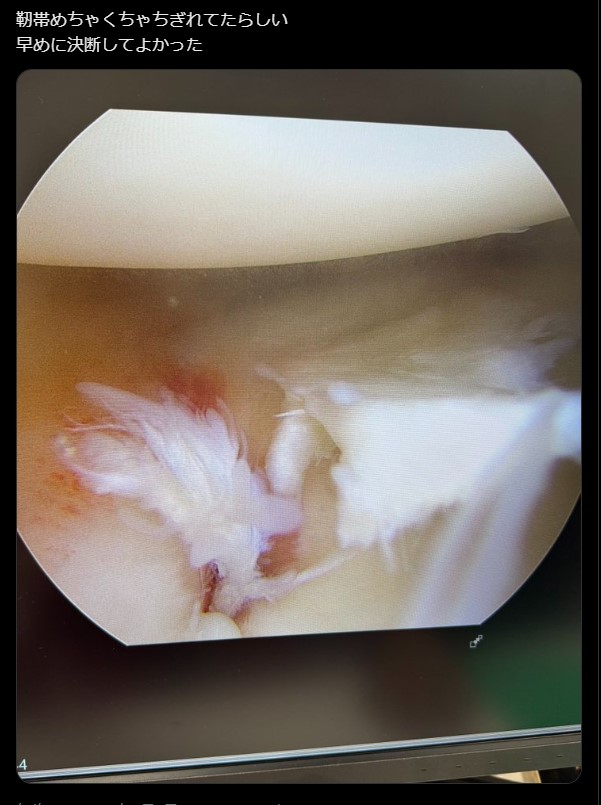

これは痛そう!平本のちぎれた靭帯(3月6日、@renhiramotoXXより)